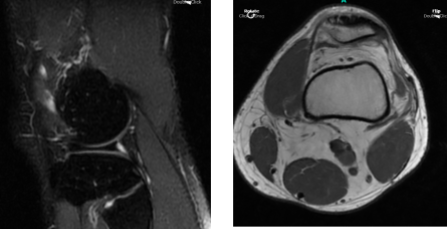

The patient presented MRI thaw showed full-thickness cartilage fissure trochlea with underlying subchondral bone marrow edema and small subchondral cysts.

MRI Left Knee Non-contrast